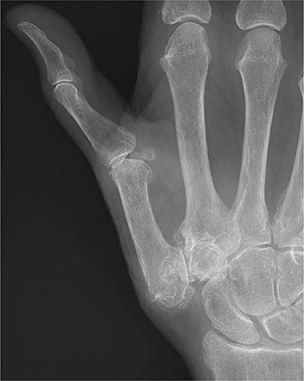

Het CMC-I-gewicht is een zadelgewricht met een grote bewegingsvrijheid, maar beperkte ossale stabiliteit. De stabiliteit is grotendeels afhankelijk van de werking van spieren, ligamenten en het gewrichtskapsel. Vooral tijdens de pincetgreep verkeert het gewricht in een minder stabiele positie. Op bepaalde delen van het gewricht kan meer wrijving ontstaan, met als gevolg kraakbeenschade. 3 Daarnaast functioneert de hefboomwerking in het nadeel van het CMC-I-gewricht. Wanneer je een voorwerp van 1 kilogram tussen duim en wijsvinger vastpakt, krijgt het CMC-I-gewricht een twaalfmaal grotere kracht te verwerken [figuur]. 4